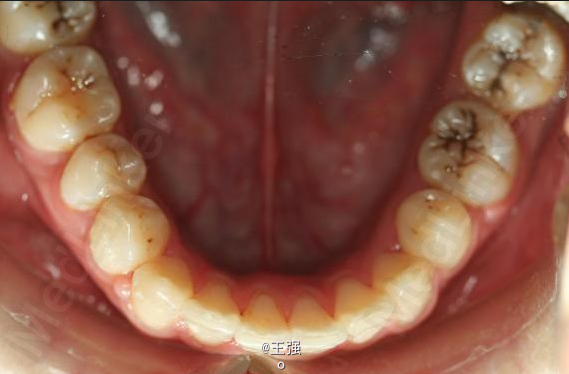

又一例不对称拔牙

牙弓狭窄,牙列拥挤

不对称拔牙